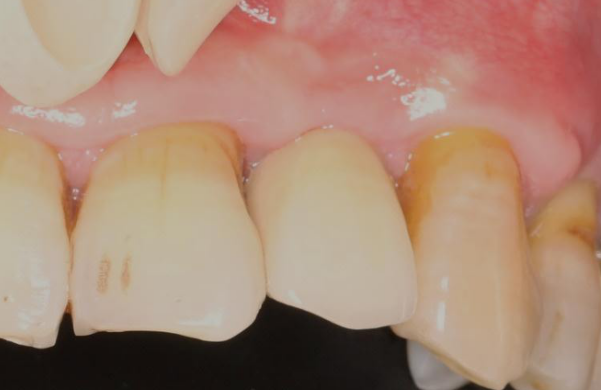

口内检查:全口牙龈轻度吸收,牙列不齐,12、22反合,口腔卫生一般。

主诉牙情况:22牙体颜色稍变暗,  松动 III 度,叩诊(-),牙 龈无红肿、溢脓、牙周袋 6mm,近远中龈乳头缺损。